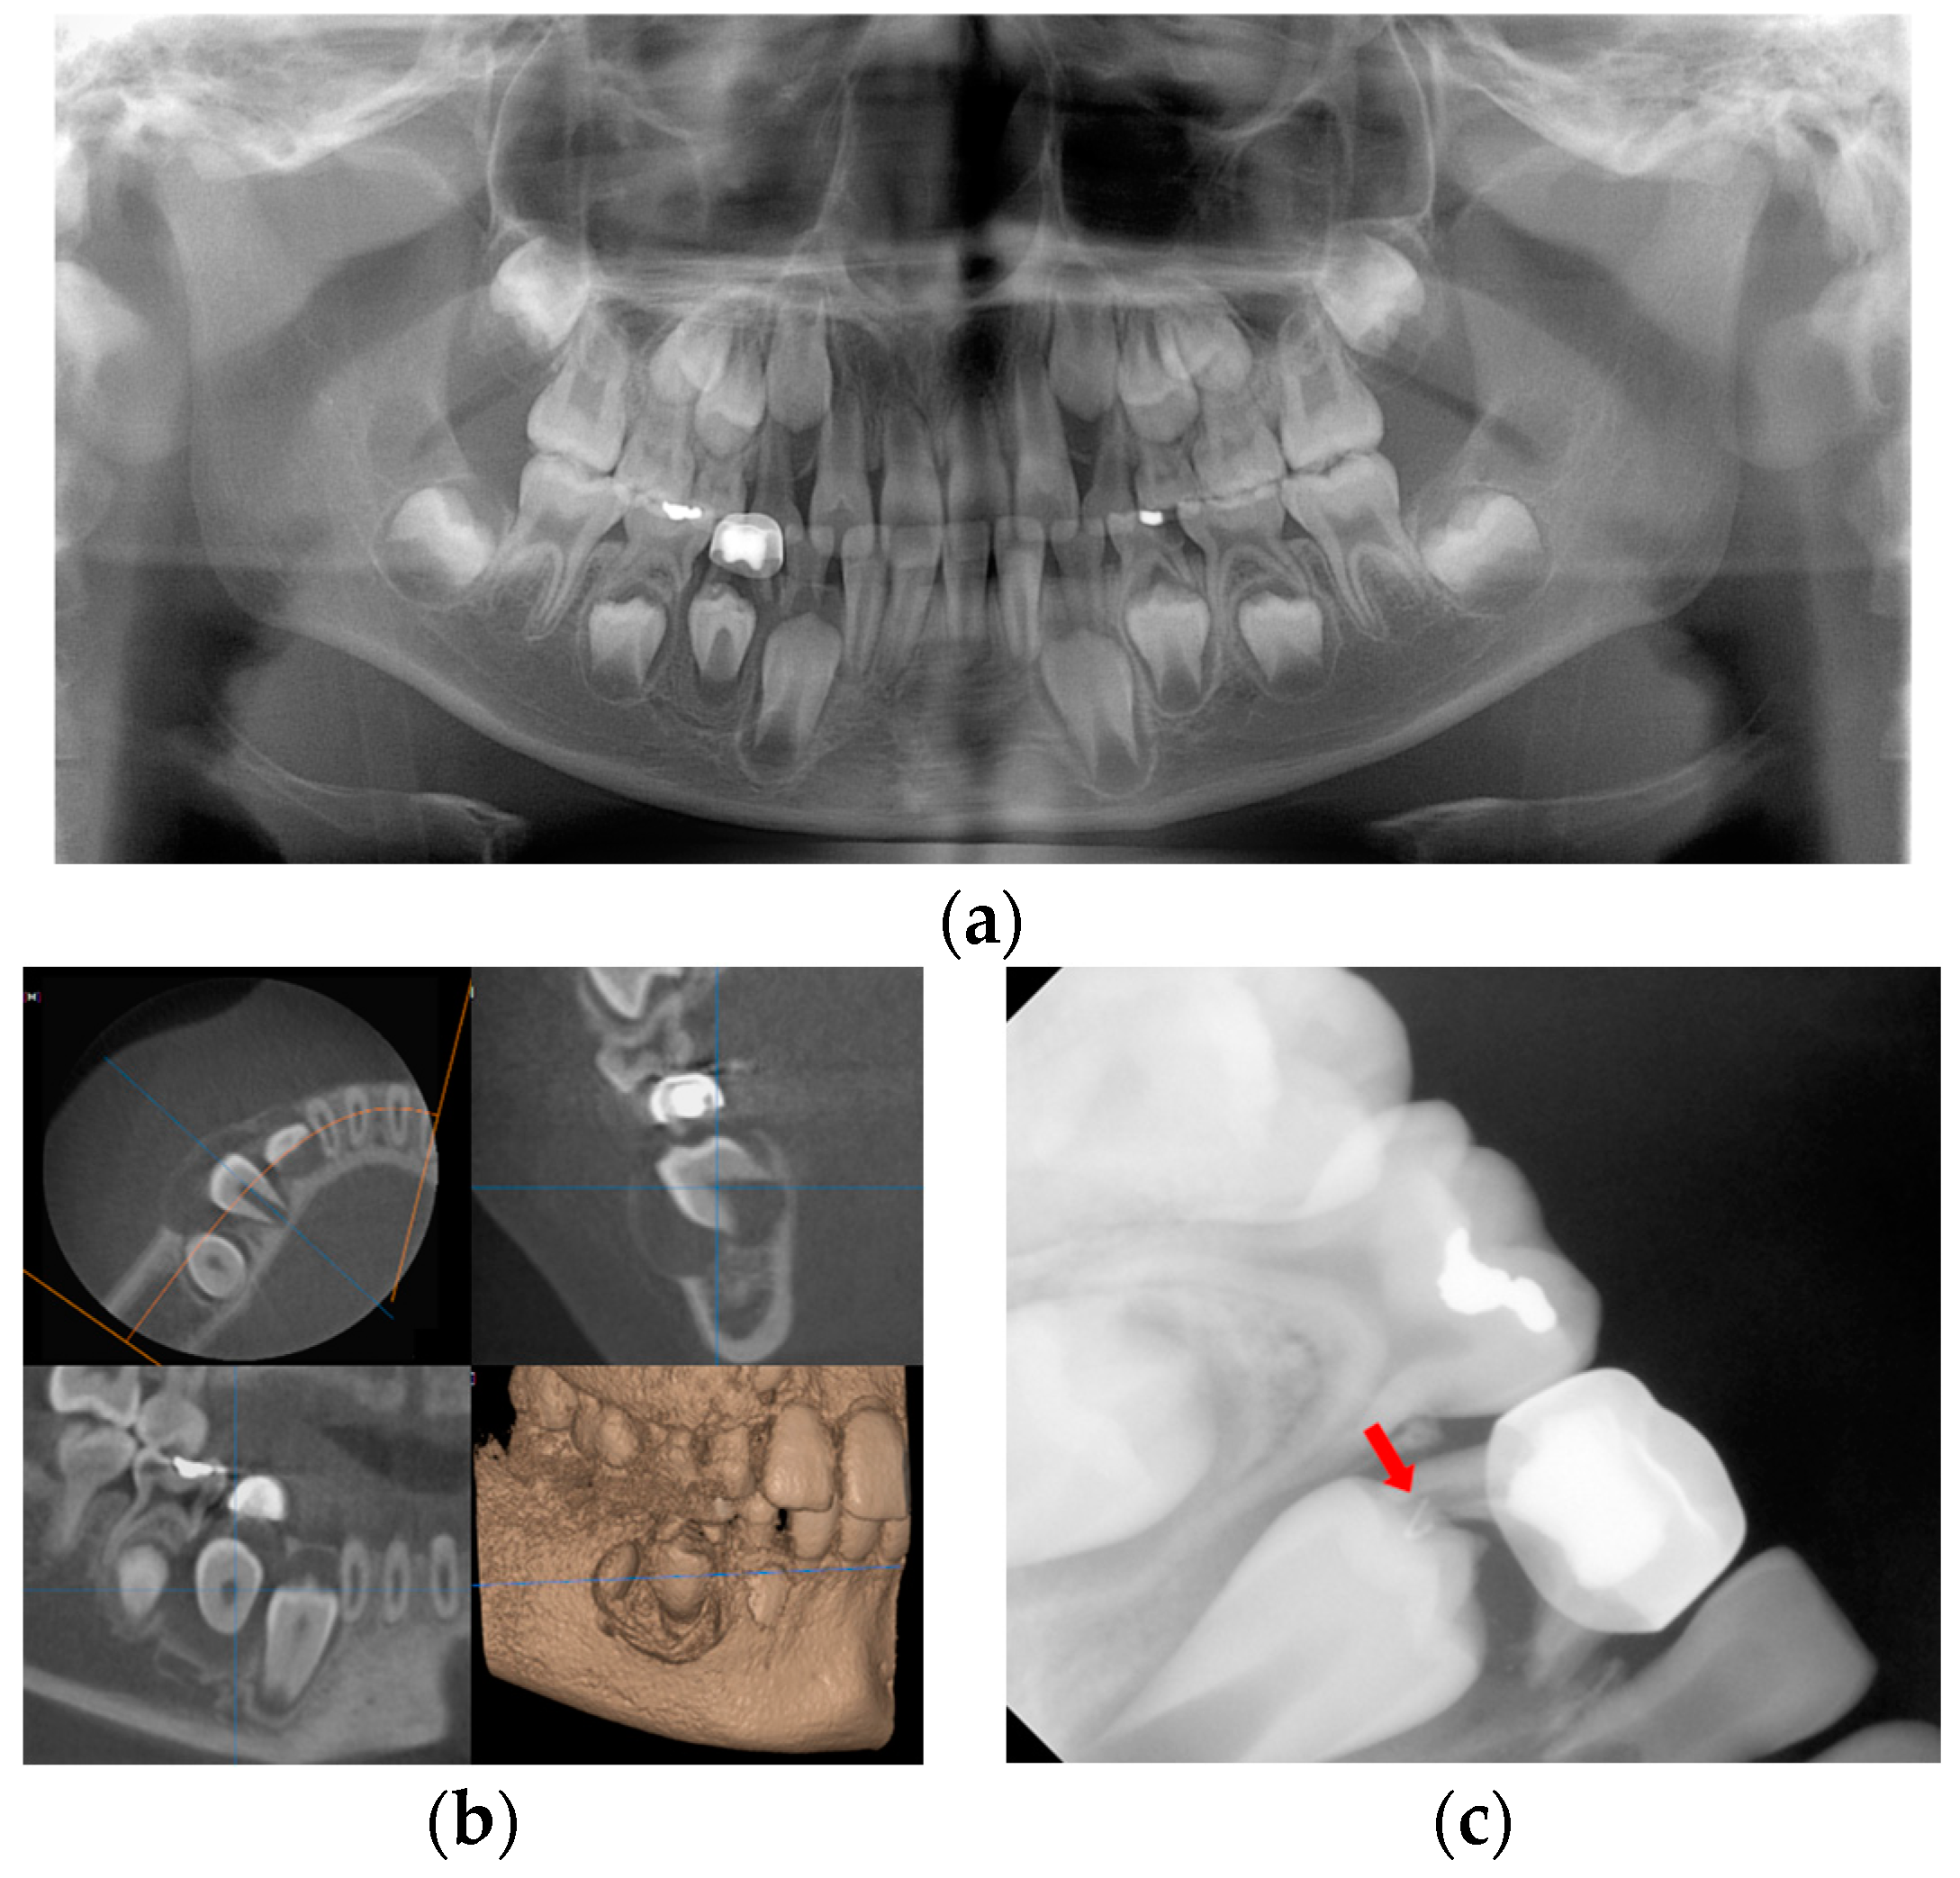

An 8-year-old girl was referred to the Department of Pediatric Dentistry of Kyung Hee University Dental Hospital at Gangdong from a local dental clinic for the treatment of a cystic lesion in the left mandibular primary molar area. Her medical history was unremarkable. According to the referral from the local dental clinic, her dental history was a pulpectomy with root canal filling with Vitapex® and restoration with a stainless-steel crown on the left mandibular primary molar 3 years ago. An endodontic retreatment was performed due to a recurrent periapical abscess that occurred 16 months after the initial treatment at the local clinic. Nevertheless, due to the residual periapical lesion and severe tooth mobility, the teeth were extracted one year after the retreatment at the local clinic. Radiological examination revealed a well-defined osteolytic lesion involving the premolars and radiopaque overfilling materials (Vitapex®) around the involved premolars (Figure 4a). Cone-beam computed tomographic (CBCT) view, cortical bone thinning, and expansion of the lesion were observed (Figure 4b).

Figure 4.

Initial visit: (a) panoramic radiograph; (b) cone-beam computed tomography. The cystic lesion around the successive left mandibular premolars can be seen, and extruded canal filling materials are also observed.

Due to the large size of the cyst, marsupialization to preserve the permanent teeth was planned. Under general anesthesia, marsupialization and incisional biopsy were conducted. The drain was inserted into the cyst cavity and sutured to maintain the openness of the lesion. The biopsy result was a benign cyst with an abscess.

Six months after treatment, the cyst size was significantly reduced, and the premolars had erupted (Figure 5). Thirty months after treatment, the extruded canal filling material remained around the roots of the erupted left mandibular premolars (Figure 6). The patient showed no clinical symptoms.

Figure 5.

Six months after marsupialization: (a) periapical radiograph; (b) intraoral photo. Left mandibular premolars have erupted and extruded canal filling materials still exist.

Figure 6.

Thirty months after marsupialization. Panoramic radiograph. The extruded canal filling materials remain around the root of the erupted left mandibular premolar.